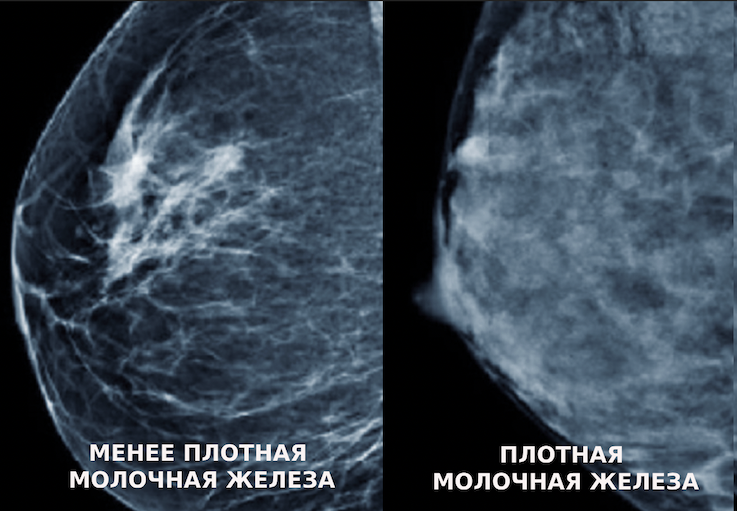

На иллюстрации представлены результаты маммографии менее плотной (жирной) груди слева и более плотной справа. Плотные молочные железы отличаются повышенной белой окраской на снимках, из-за чего мелкие раковые образования белого цвета сложнее выявить на ранних этапах заболевания.

В результате снижения чувствительности метода изображения раковых образований становятся неразличимы среди здоровой ткани, так как обе отображаются белым цветом на рентгеновских снимках.